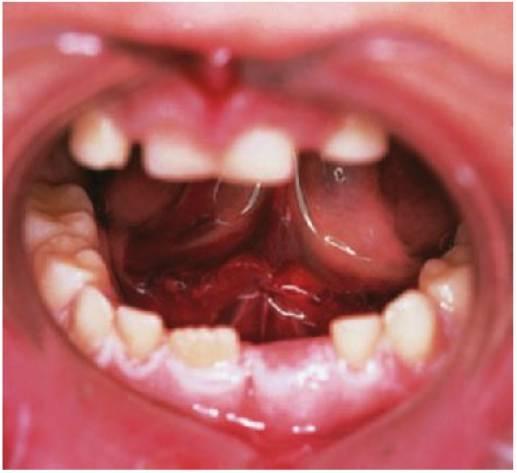

El tratamiento de los traumatismos dentoalveolares, que suele resultar angustioso para los niños y para los padres (fig. 7.1), con frecuencia resulta también difícil para el especialista, si bien se encuentra entre las causas más habituales de visita del niño al odontopediatra. La urgencia del paciente debe constituir una rutina para el especialista y siempre debe elaborar se un exhaustivo examen del niño antes de comunicar a los padres las eventuales necesidades de tratamiento, pues muchos casos podrían carecer de la gravedad que parecía en un principio. Ante todo, se debe tranquilizar tanto a los padres como al niño, pues un traumatismo no sólo compromete una dentición sana, sino que puede también ocasionar un defecto que afecte a la autoestima y a la calidad de vida del paciente y le obligue a un mantenimiento odontológico de por vida.

La región orofacial sufre la mayor afectación de traumatismos durante los episodios de maltrato infantil (fig. 7.2) y estos traumatismos no accidentales tienen como resultado diferentes tipos de lesiones, como las lesiones que no concuerdan con el relato ofrecido, los hematomas en tejido blando que no cubren prominencias óseas, las lesiones que adquieren la forma de un objeto reconocible o la multitud de lesiones que aparecen en el mismo niño a diferentes edades; asimismo, las marcas de mordeduras en niños se consideran maltrato infantil hasta que se prue be lo contrario. Para establecer la adecuada notificación, tratamiento y prevención de más lesiones, deben ser del total conocimiento del especialista tanto las características y las conclusiones del diagnóstico de maltrato infantil como el protocolo para denunciar tales hechos.